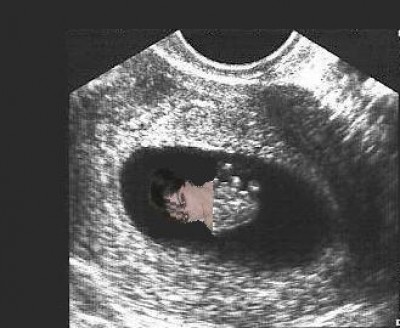

We had a little scare on Friday and I was given an early ultrasound. Fortunately, everything looked good. Baby measured just right for it's age (about 8wks) at 1.5cm and the little heart was beating along at a steady 145bpm (also very good). Everything else looked good as well. I thought I would include a picture for anyone interested.

baby2.jpg

baby2.jpg [ 19.12 KiB | Viewed 4381 times ]